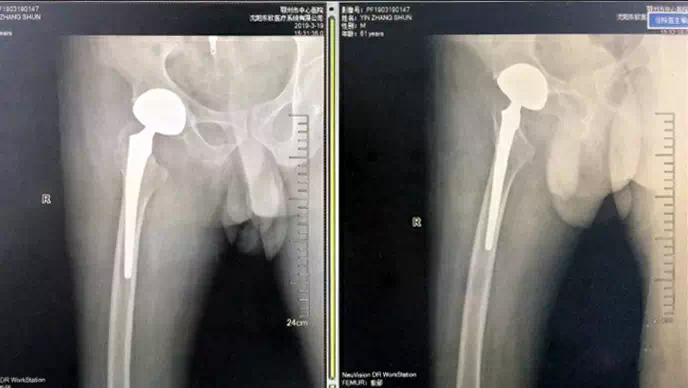

(术后X光片)